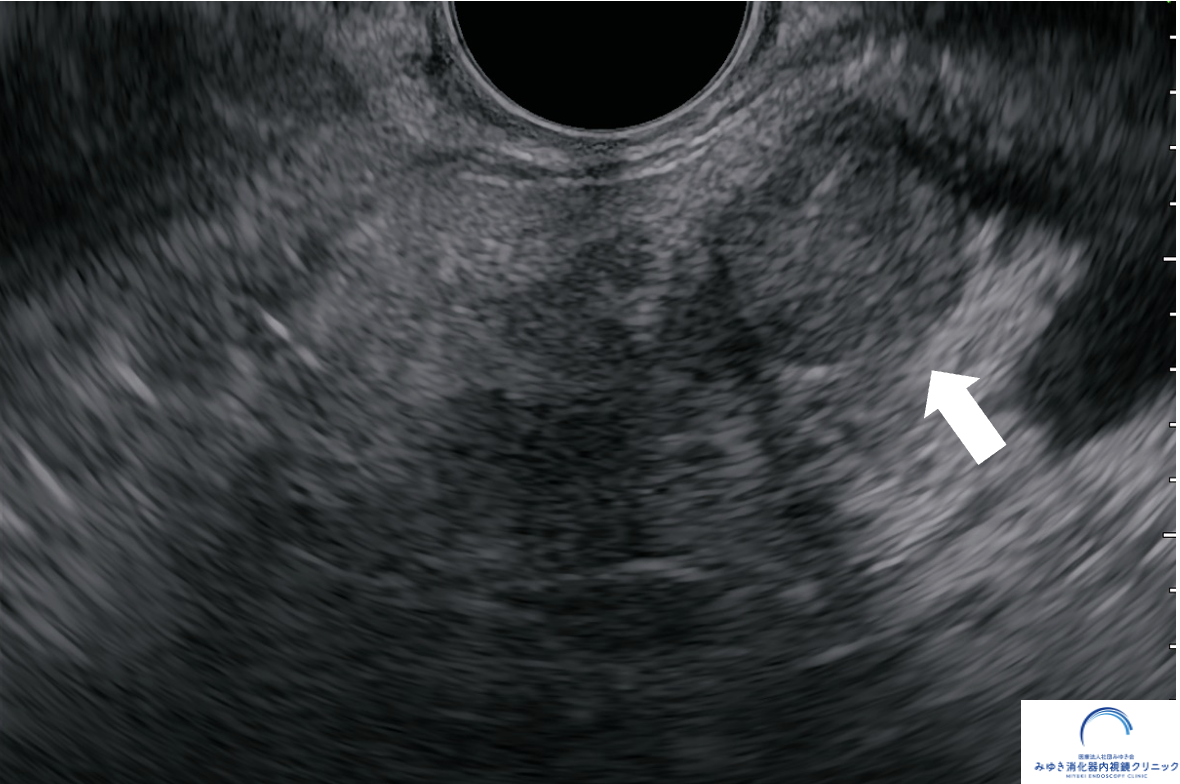

症例:小さな膵がんが見つかったケース

他院の腹部エコーで膵嚢胞を指摘され、当院で超音波内視鏡(EUS)による精密検査を行いました。

他院の腹部エコーで膵嚢胞を指摘され、当院で超音波内視鏡(EUS)による精密検査を行いました。膵臓に約10mmの腫瘍を認め、超音波内視鏡下穿刺吸引法(EUS-FNA)でがん細胞を確認しました。手術の結果、ステージ1の膵がんと診断され、早期発見につながった症例です。

このように、通常の検査では見つかりにくい小さな病変も、EUSによって発見できることがあります。